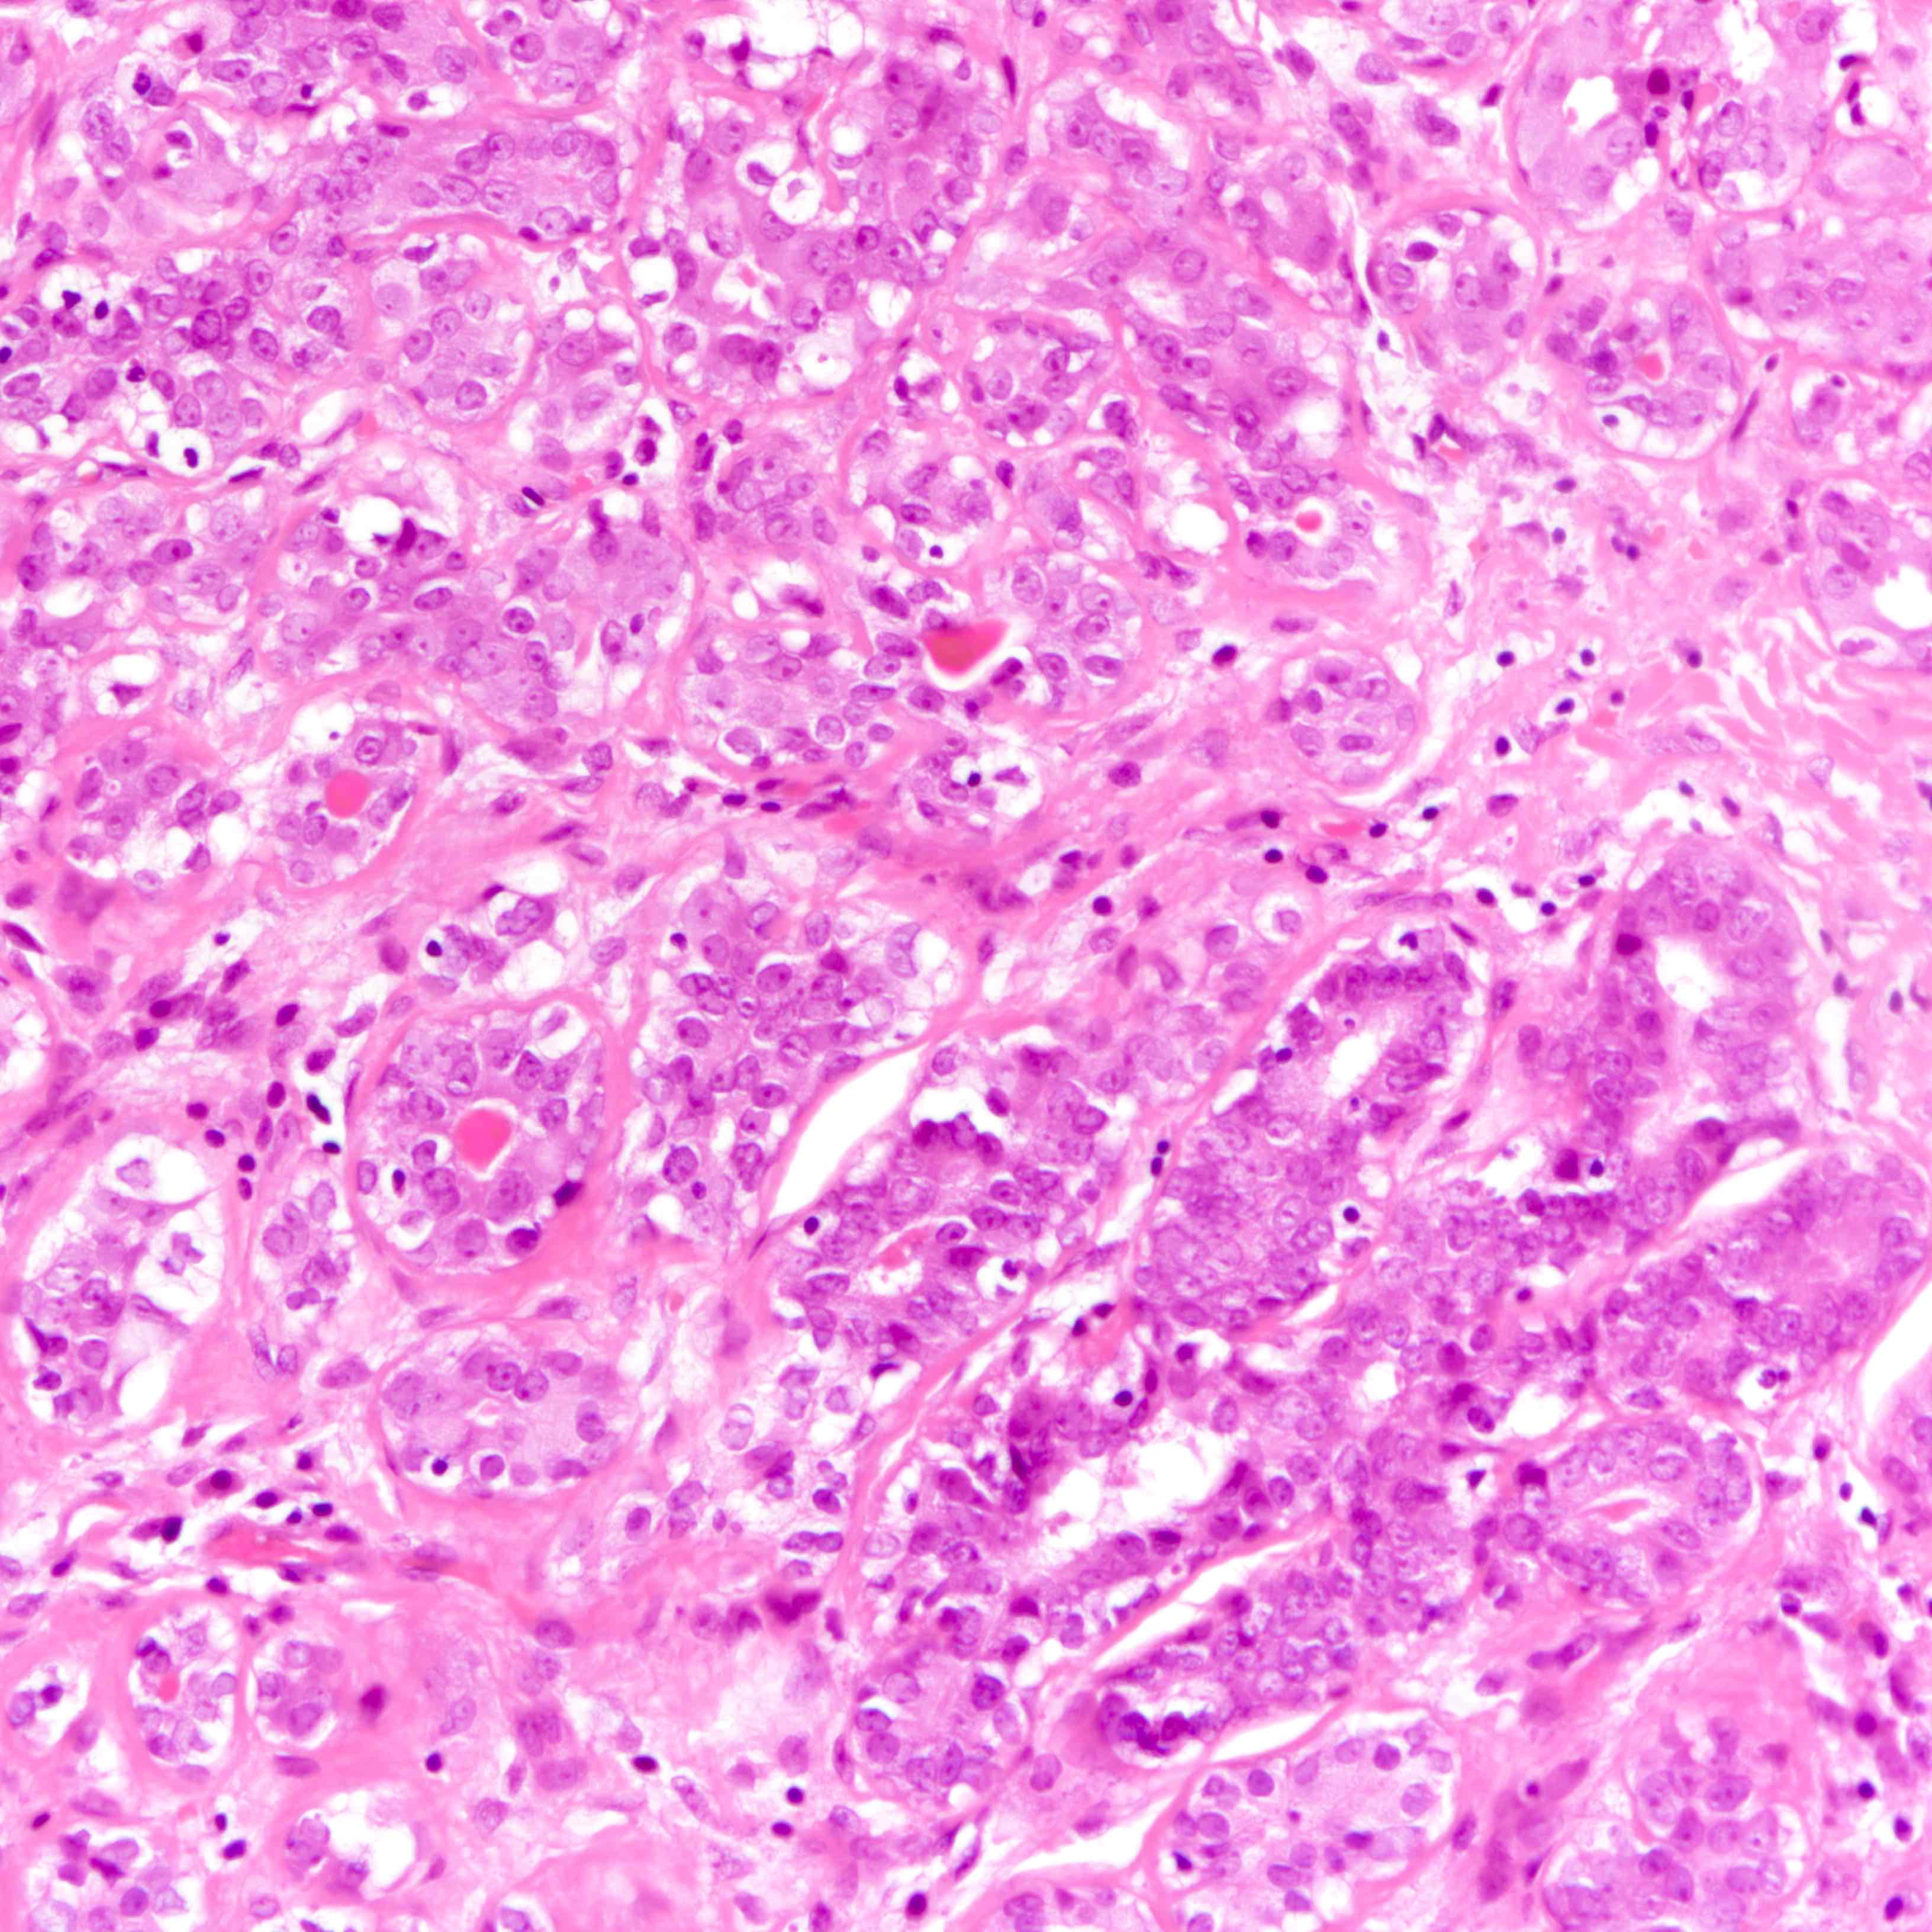

- Sparse fibrovascular stroma intervening tubules

- Small, uniform, closely packed round tubules (Clin Med Insights Pathol 2018;11:1179555718757499)

- Lined by an inner layer of luminal epithelial cells and an outer layer of myoepithelial cells

- Rare mild atypia and mitotic figures does not exclude diagnosis

- Occasional luminal eosinophilic secretion

- Lined by an inner layer of luminal epithelial cells and an outer layer of myoepithelial cells

Microscopic (histologic) images

Contributed by Joshua J.X. Li, M.B.Ch.B. and Gary M. Tse, M.B.B.S.

Contributed by Jijgee Munkhdelger, M.D., Ph.D. and Andrey Bychkov, M.D., Ph.D.